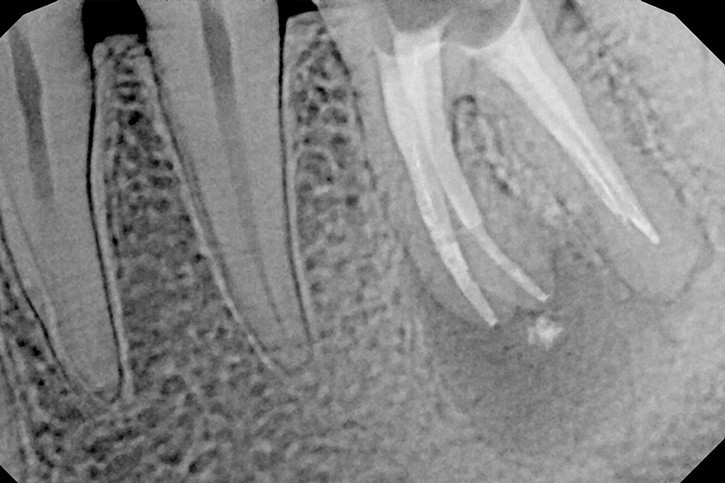

Na podstawie zdjęcia rentgenowskiego określa się kształt i długość kanału bądź za pomocą specjalnego urządzenia mierzy się jego długość. Potem lekarz otwiera wejścia do kanału, chroniąc ząb koferdamem, czyli specjalną gumą, zapewniającą sterylność oraz chroniącą przed środkami chemicznymi służącymi do oczyszczania kanału. Używa się do tego zarówno specjalistycznego sprzętu, jak i nowoczesnych mikroskopów, pozwalających na uzyskanie dokładnego obrazu leczonego zęba. Ostatnią czynnością jest wypełnienie materiałem światłoutwardzalnym i zabezpieczenie zęba przed dostaniem się i rozwojem bakterii mogących wywołać wtórny stan zapalny.

By uniknąć niedokładności leczenia, oprócz sumiennego wykonania procedur należy diagnostycznie kontrolować każdy etap leczniczy przy użyciu rtg. Szansą dla niedokładnie wypełnionego kanałowo zęba jest jego powtórne leczenie endodontyczne, zwane REENDO.

Najczęstsze przyczyny utrudnień lub niepowodzenia leczenia to pozostawione w kanałach zębów złamane narzędzia endodontyczne po uprzednim leczeniu, obliteracja, czyli bardzo słaba drożność kanałów korzeniowych lub wręcz jej brak, do której dochodzi na skutek przewlekłych stanów zapalnych miazgi, czy wreszcie niestandardowa anatomia zęba.

Konieczność powtórnego leczenia endodontycznego może zaistnieć w sytuacji, gdy kanały zęba nie zostały wypełnione do ich anatomicznego wierzchołka lub w trakcie leczenia doszło do złamania i pozostawienia ułamanego narzędzia w świetle kanału korzeniowego. O konieczności powtórnego leczenia endodontycznego może również zadecydować zmiana zapalna przy wierzchołku korzenia, która jest widoczna jedynie na obrazie kontrolnego zdjęcia rtg.